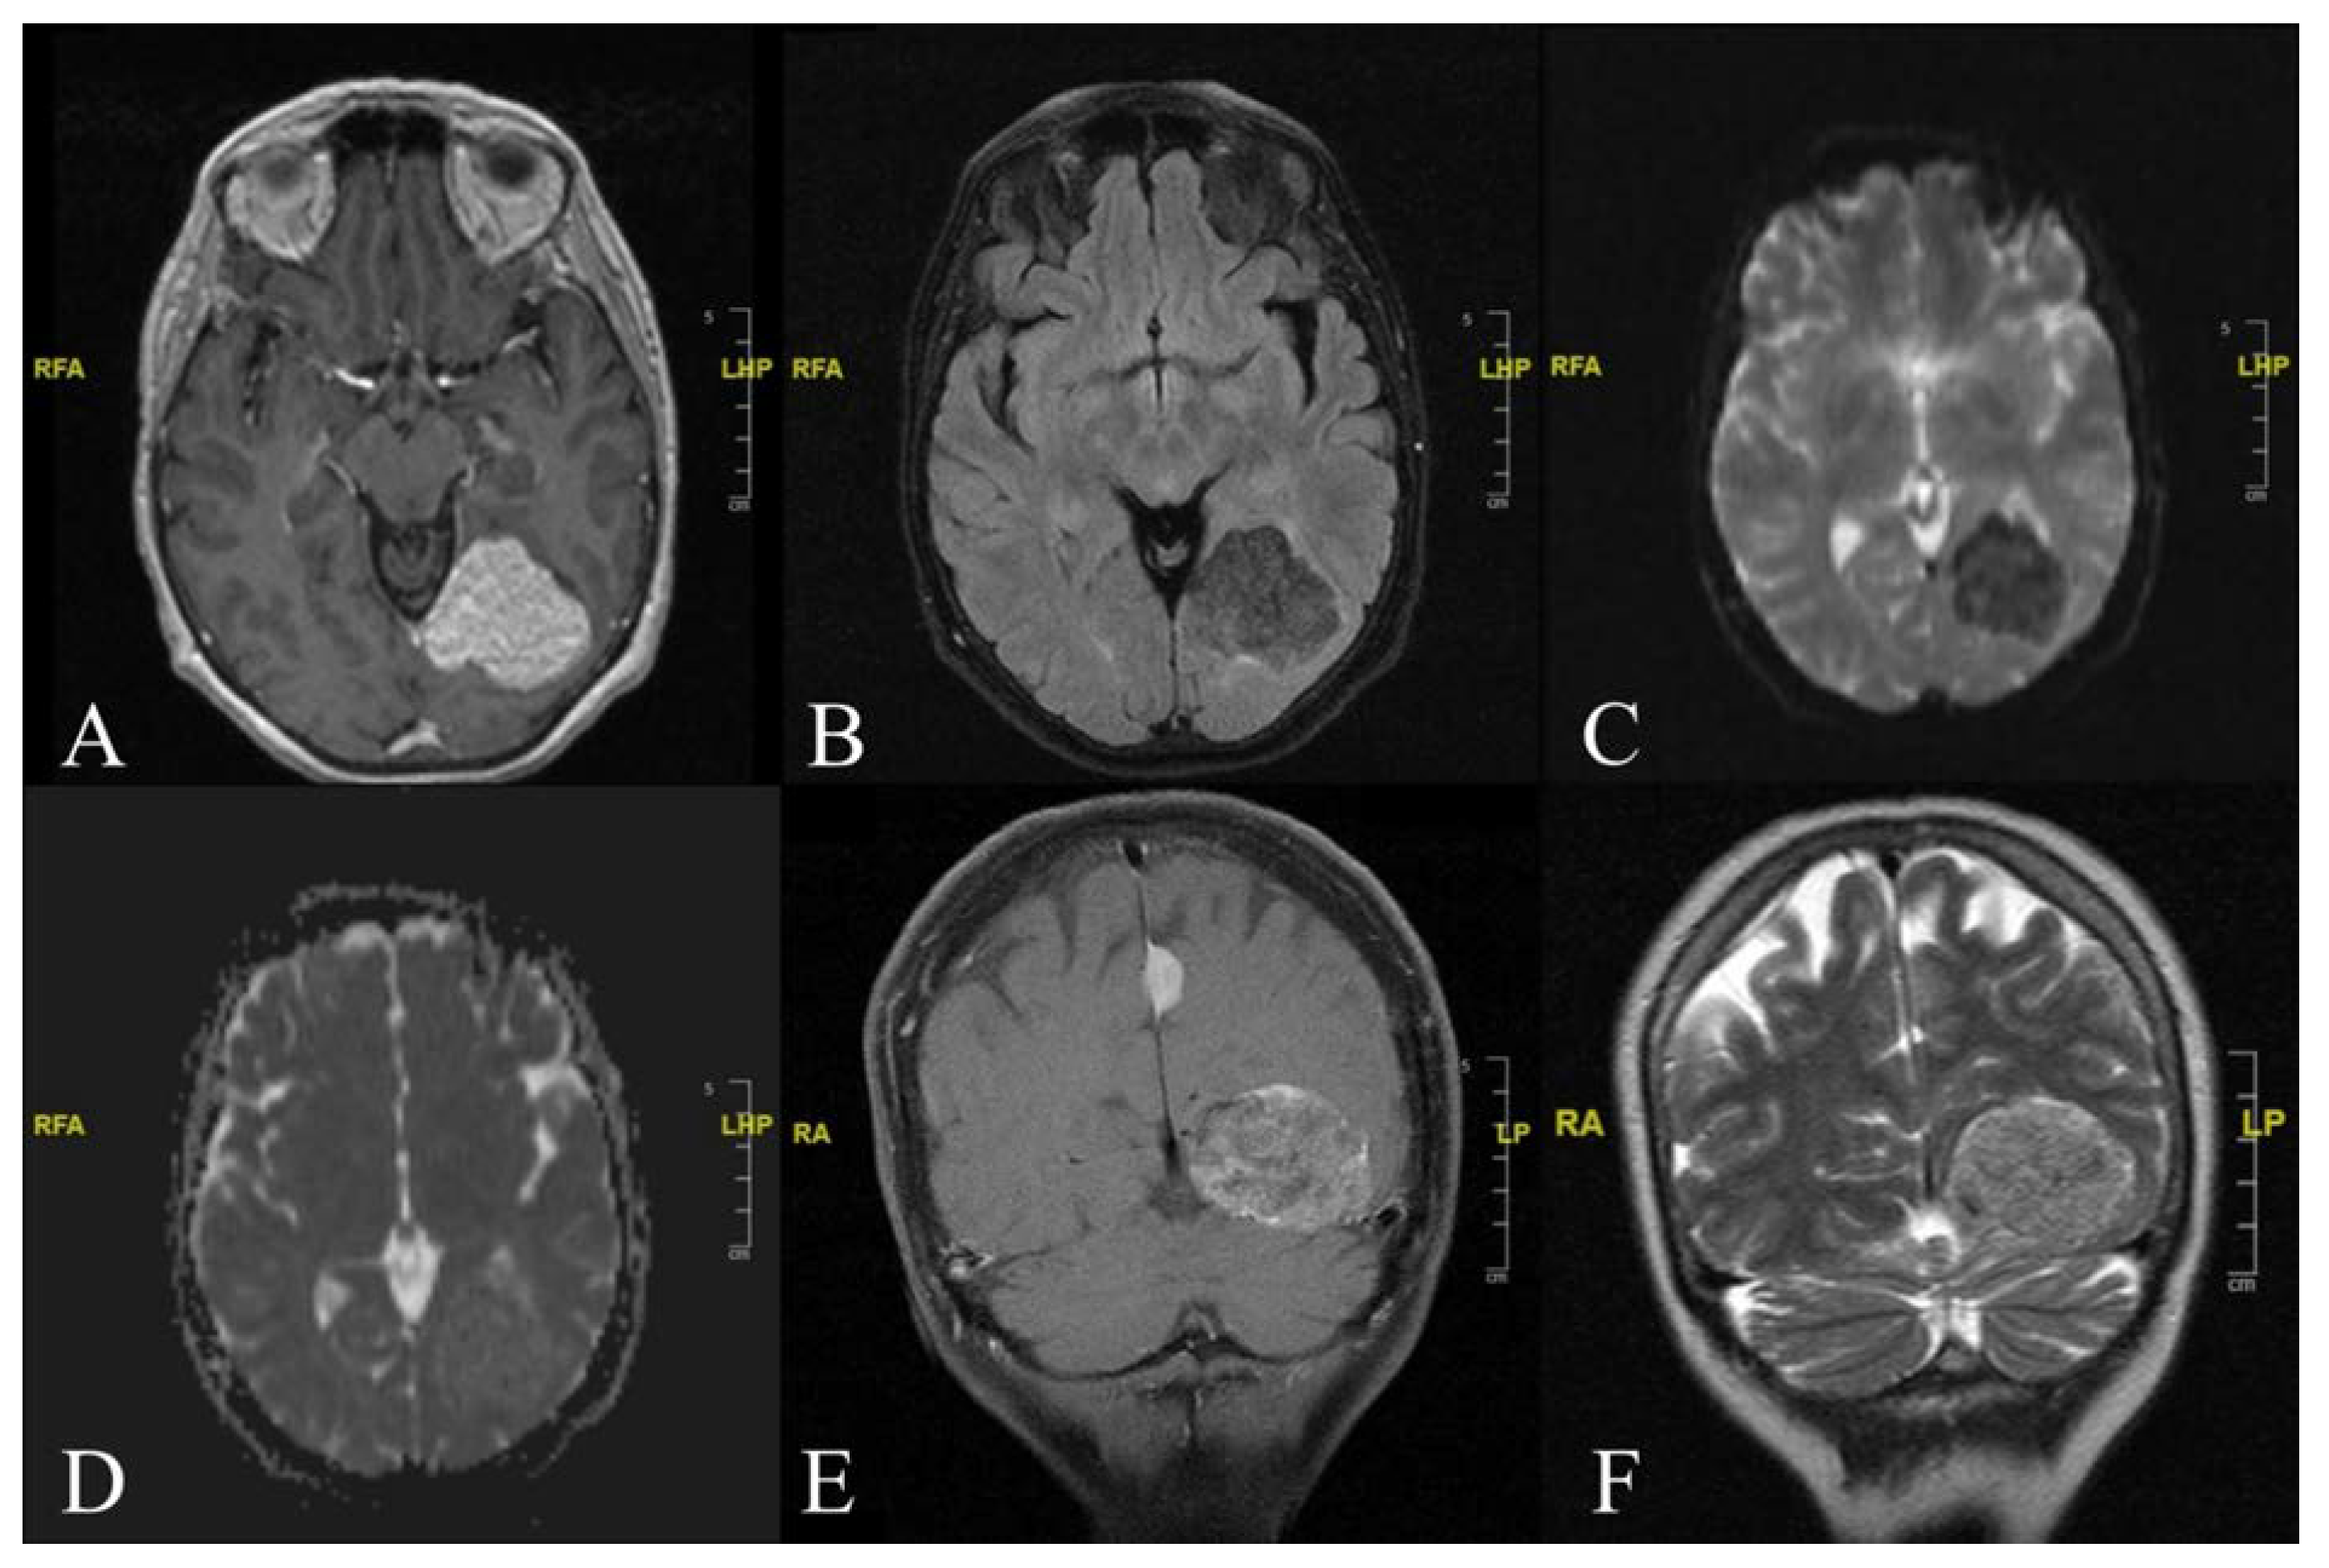

Visual Aura Secondary to Supratentorial Lipomatous Meningioma: A Rare Case Report

2. Case Report